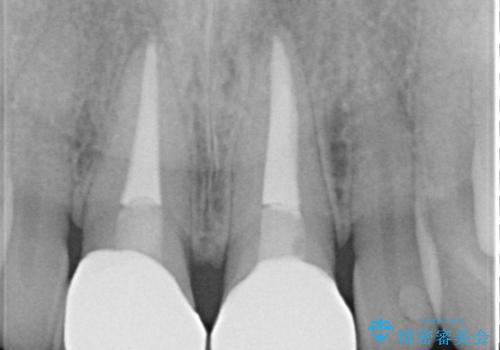

前歯に違和感や根尖病巣(根の先に細菌が溜まっている)が認められたため、治療をご提案しました。

根管治療について

保険根管治療は回数がかかることが多く、終了予定がわかりにくいです。

当院では、根管治療は長い時間のご予約を頂き、多くの場合2~3回で終わります。

根管治療は歯内の治療なので患者様には見えない場所ですが、ここが細菌で汚染されると激しい痛みや長引く違和感の原因になります。

当院では、清潔な治療を徹底し、顕微鏡を使用した精密な治療を行っています。

症状や根管の状態により、治療金額が異なります(5~10万円目安)。治療回数による費用負担の増減はありません。